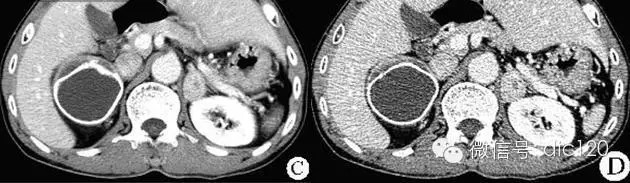

【影像表现】 CT检查可见右侧肾上腺区较大圆形肿块。直径约5cm。肿瘤密度均一,内部呈囊性表现,边缘环形高密度钙化。增强检查,动脉期肿瘤内低密度区无强化。静脉期肿瘤内低密度区强化不明显,延迟扫描肿瘤内低密度区可见强化,冠状面重建可见肾上腺区圆形、边界清晰的肿块影。 USG:声像图表现为肾上腺区较大的类圆形肿块,呈囊性中等回声,考虑合并坏死,其内有液性无回声区。

CT:CT对肿瘤定位可提供较准确信息,诊断准确率高,为常用检查方法。多表现为一侧肾上腺较大圆形或椭圆形肿块,偶为双侧性。直径常为3~5cm,或更大。较小肿瘤密度均一,类似肾脏密度;较大肿瘤常因坏死或陈旧性出血而密度不均,内有单发或多发低密度区,甚至呈囊性表现。少数肿瘤可有高密度钙化灶。增强检查,肿瘤实体部分明显强化,其内低密度区无强化。肾上腺圆形或分叶状、边界清晰的实性肿块影,肿瘤大小不定,较大肿瘤可以发生液化、坏死及出血。增强扫描实性部分呈明显强化。